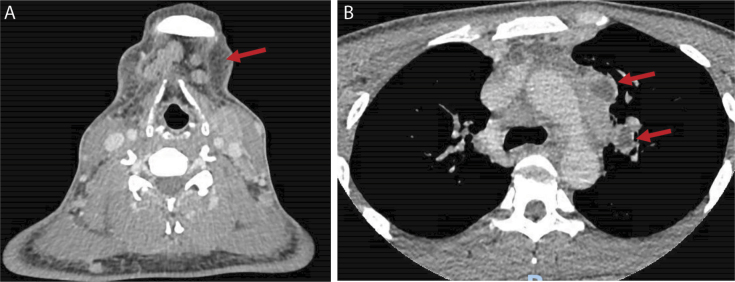

干扰素-γ (IFN-γ)自身抗体综合征是一种新兴的临床实体,与播散性非结核分枝杆菌感染(dNTM)有关,特别是在健康年轻人中,这一人群以前未被认为具有特别的风险。一名29岁东南亚男子在一艘国际货船上工作时出现数周的发热、咳嗽、淋巴结病和体质症状,病情迅速恶化并出现败血症样综合征。淋巴结和痰培养最终诊断为dNTM感染,同时生长有仙桃分枝杆菌和脓肿分枝杆菌。他开始使用利妥昔单抗和联合抗分枝杆菌治疗,临床反应良好。该病例突出了dNTM患者在IFN-γ自身抗体背景下面临的一些困难,特别是诊断延迟,以及缺乏围绕最佳管理的证据基础。需要对长期结果和治疗进行进一步研究,并提高临床医生的认识。

Interferon-gamma (IFN-γ) autoantibody syndrome is an emerging clinical entity that has been associated with disseminated non-tuberculous mycobacterial infection (dNTM) particularly in healthy young people, a population not previously thought to be at particular risk. A 29-year-old South-East Asian man presented with several weeks of fever, cough, lymphadenopathy, and constitutional symptoms while working on an international cargo ship, deteriorating rapidly with a sepsis-like syndrome. Eventually lymph node and sputum cultures revealed a diagnosis of dNTM infection with growth of both Mycobacterium persicum and Mycobacterium abscessus. He was commenced on rituximab as well as combination anti-mycobacterial therapy with good clinical response. This case highlights some of the difficulties faced by patients with dNTM in the context of IFN-γ autoantibodies, particularly delayed diagnosis, and lack of evidence base surrounding optimal management. Further research into long-term outcomes and treatment is required as well as increased awareness among clinicians.